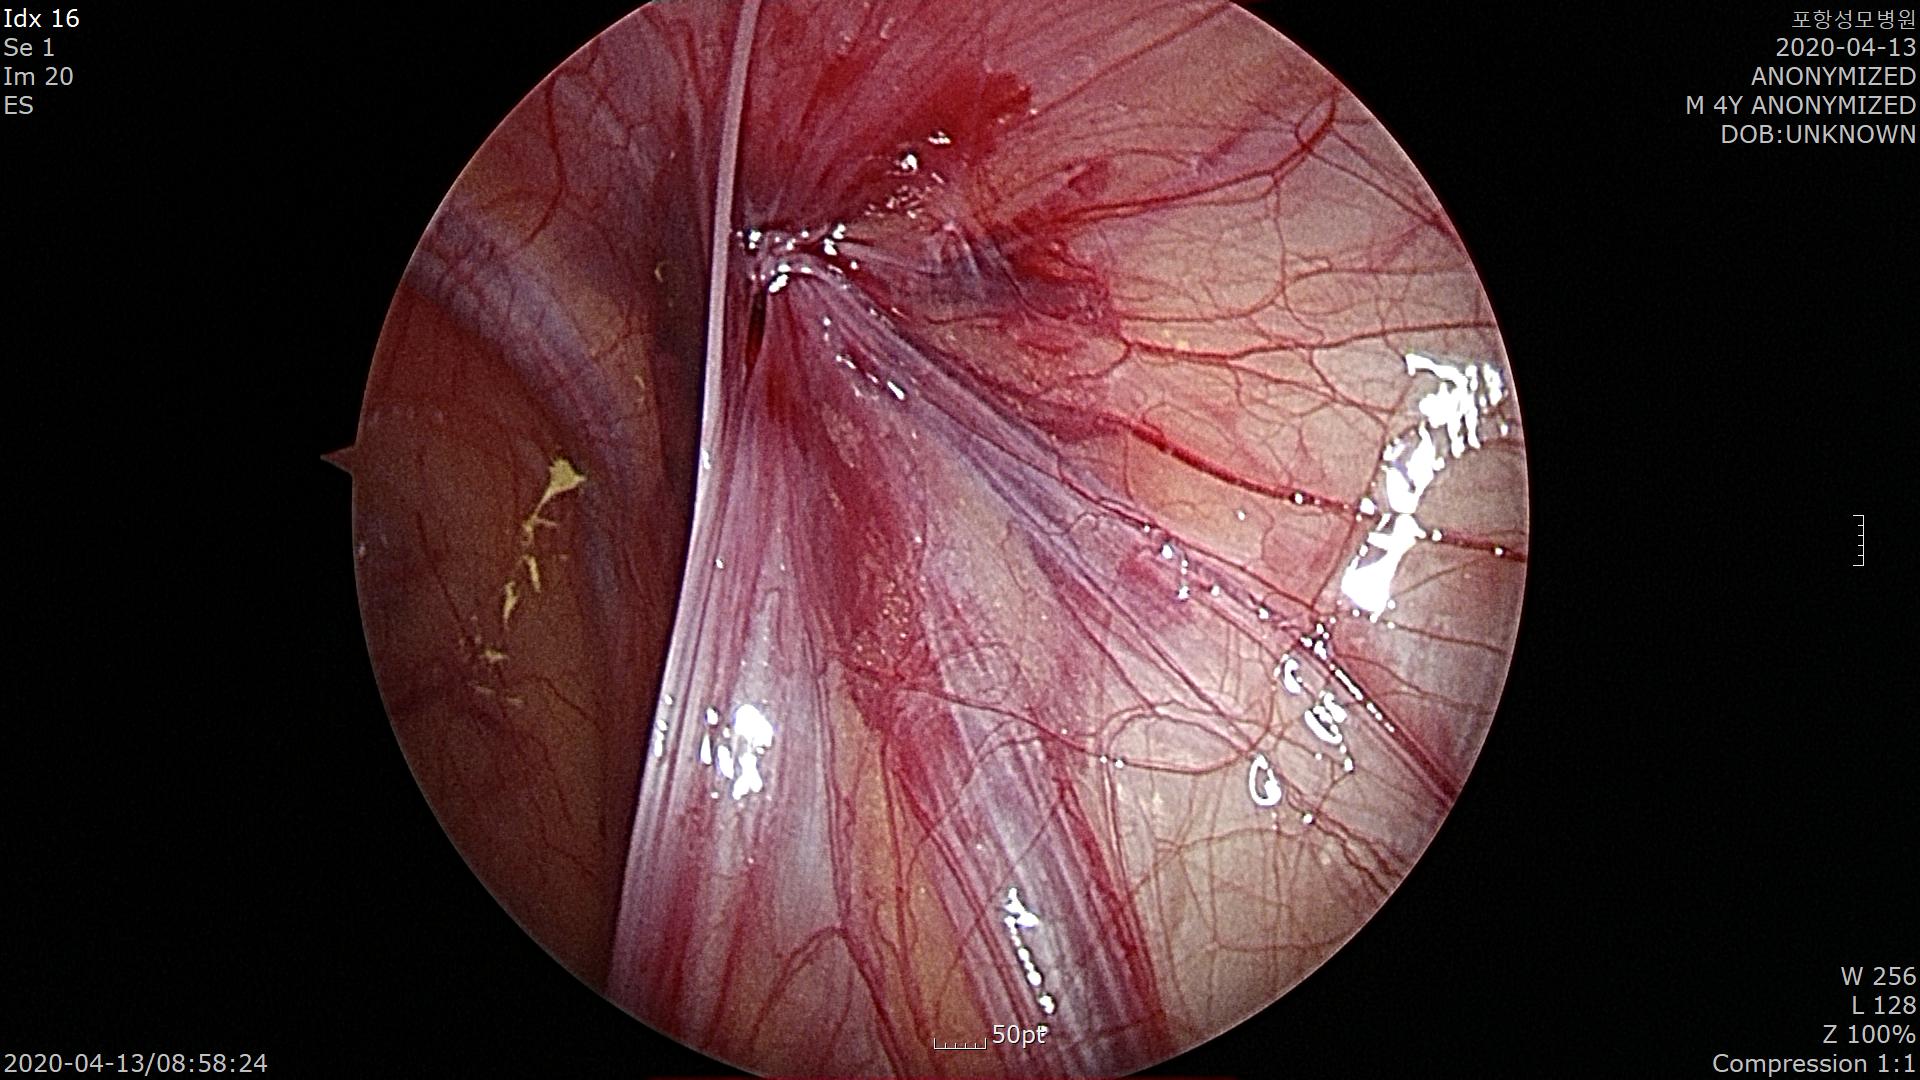

수술을 끝내기 전에 반대편 서혜부 탈장이 없는지 확인합니다.

역시나 왼쪽 서혜부에도 탈장이 동반되어 있습니다.

양측성 탈장이며 오히려 증상이 있는 오른쪽 서혜부 탈장보다 증상 없는 왼쪽 탈장구멍이 더 큽니다.

수술중에 약 40% 확률로 양측 서혜부 탈장이 확인됩니다.

역시 좌측 서혜부 탈장구멍을 봉합한 기법으로 특수한 바늘을 이용하여 고위결찰(High ligation)을 시행합니다.

탈장구멍이 잘 봉합되었네요.